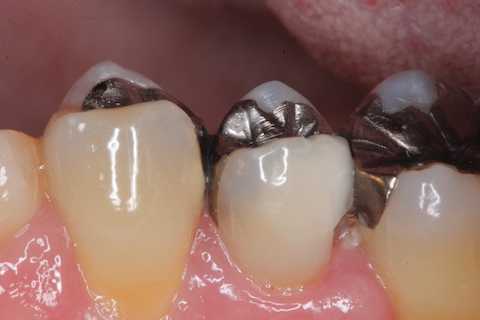

今日の充填治療55(遠心隣接面カリエス) 2023.12.21